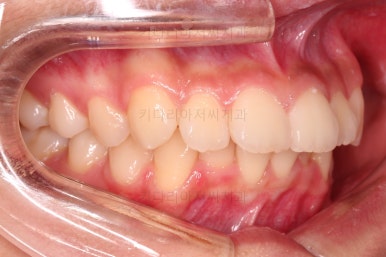

1. 초진 시 입안의 모습 평가

부산치아교정치과 키다리아저씨치과에 처음 내원했을 당시의 입 안의 모습입니다.

전반적으로 윗니가 나와있는 양상이고요.

앞니는 뻐드러져 있네요.

아래 앞니는 위로 솟구쳐 올라서 윗니 뒤쪽을 강하게 치고 있는 과개교합 양상이었고요.

위아래 앞니쪽이 삐뚤어져 있는 상태였습니다.

부산치아교정치과 키다리아저씨치과에서 마무리한 입안의 모습입니다.

가지런하게 잘 정렬이 되었고요.

윗니만 발치한 편악발치교정이지만 틈새 없이 공간이 닫혔으며 교합도 잘 맞습니다.